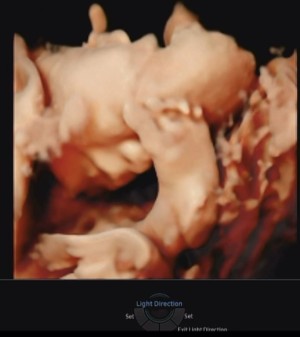

30주 입체초음파입니다 :)

이레IYRAE

2025-08-21